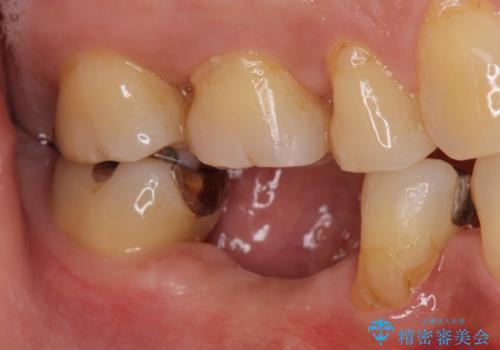

- 歯茎が腫れて痛いとの事で来院。

保存できない状態でしたので抜歯をして歯槽堤保存術を行いました。その後大臼歯部にインプラント治療を行いました。